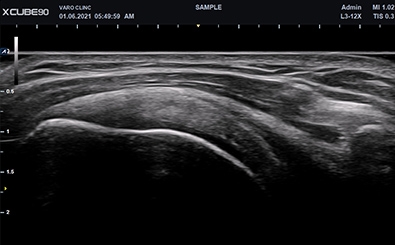

Shoulder